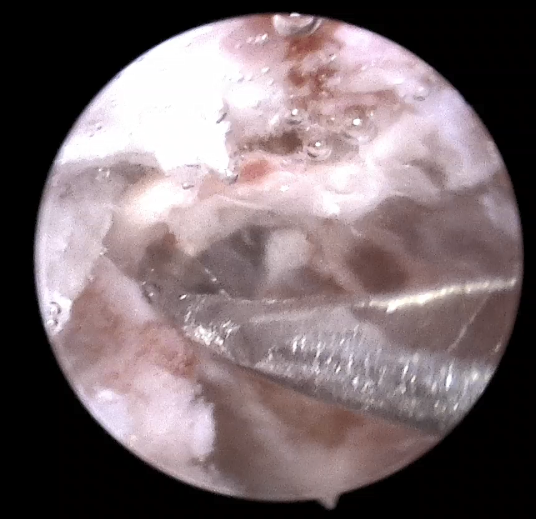

洪主任沒有采用傳統(tǒng)顯微鏡手術(shù),而是選用了從外耳道進(jìn)入,不破壞耳朵結(jié)構(gòu)、耳外無創(chuàng)傷、手術(shù)視野更開闊的耳內(nèi)鏡下手術(shù)。術(shù)中,耳內(nèi)鏡從外耳道上壁和后壁進(jìn)入,顯示屏上顯示醫(yī)生視角可達(dá)120度,并且直接抵近膽脂瘤。

(耳內(nèi)鏡下經(jīng)外耳道入路,視野開闊,可抵近觀察)

(在持續(xù)灌流模式水下操作耳內(nèi)鏡手術(shù))